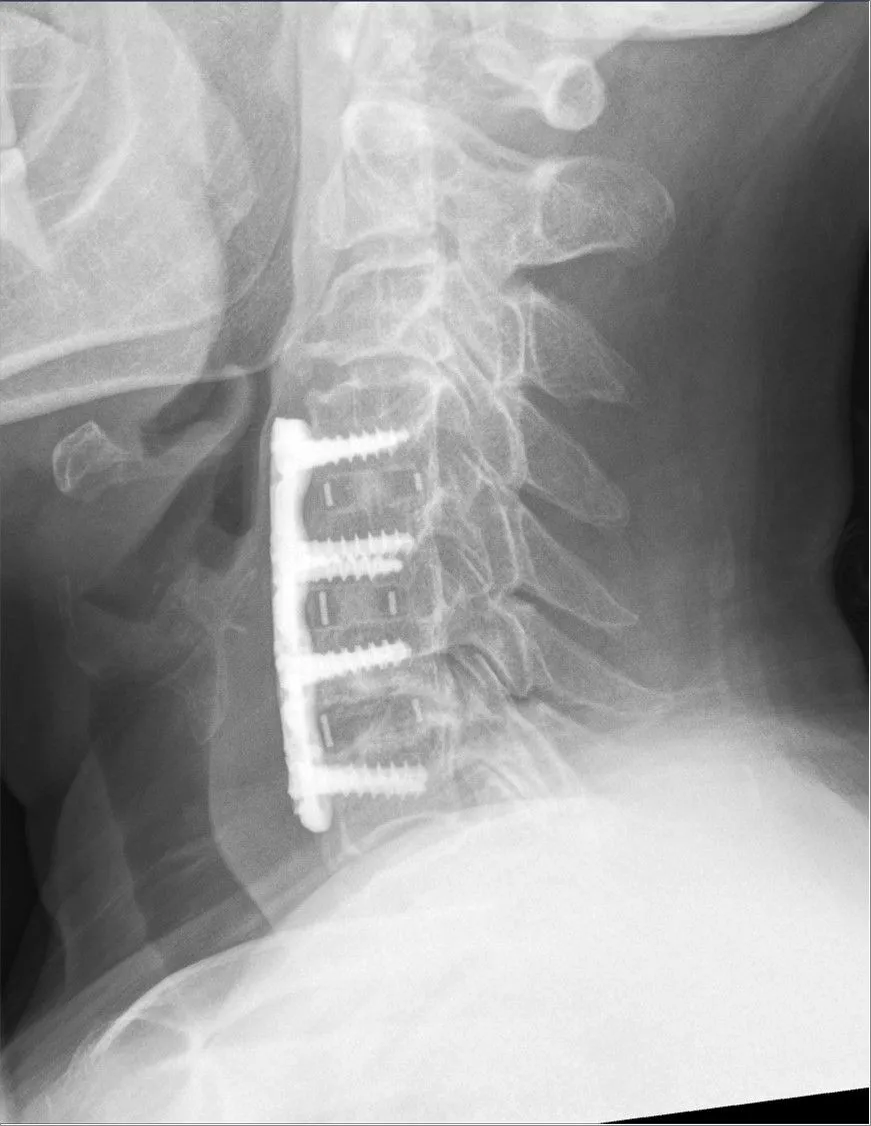

Traditional Neck Fusion: High Risk, Low Reward

ACDF carries a significant risk due to the delicate anatomy of the anterior neck. Complications, including injury to surrounding structures, are common:

- Vascular, Airway, and Neural Risks: There is risk of injury to blood vessels, the trachea, and the esophagus.

- Dysphagia and Hoarseness: Postoperative dysphagia (difficulty swallowing) is frequent, with some prospective studies reporting incidence rates as high as 60%. Other common complications include excessive neck swelling, hoarseness, and infection.

Overall Risk: While complication rates vary widely, studies document significant overall postoperative complication rates, including pseudarthrosis (failure to fuse) and worsening myelopathy.

The Long-Term Catastrophe: Adjacent Segment Disease (ASD)

The fusion process itself is fundamentally flawed. By eliminating motion at the fused segment, the stress of movement is transferred to the discs immediately above and below the fused level. This dramatically accelerates their wear, leading to ASD. This common complication often requires the patient to undergo a second, equally aggressive fusion surgery a few years later.